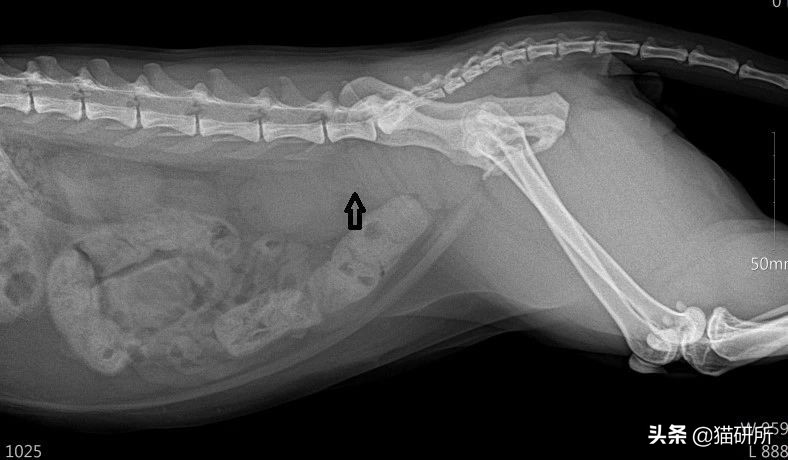

❗ 一例肿物压迫引发的猫咪便秘

(箭头)为B细胞淋巴瘤@姜医生提供